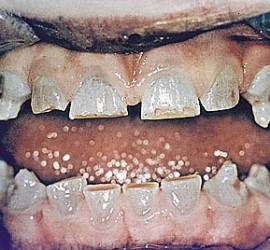

Лечение пульпита. При лечении пульпита перед врачом встают следующие задачи: избавление больного от болевых ощущений, ликвидация инфекционно-токсического очага в пульпе зуба, восстановление формы и функции зуба. Первую помощь больному острым пульпитом может оказать средний медработник или врач любого другого профиля. Она заключается в назначении внутрь обезболивающих препаратов типа анальгина, амидопирина, […]